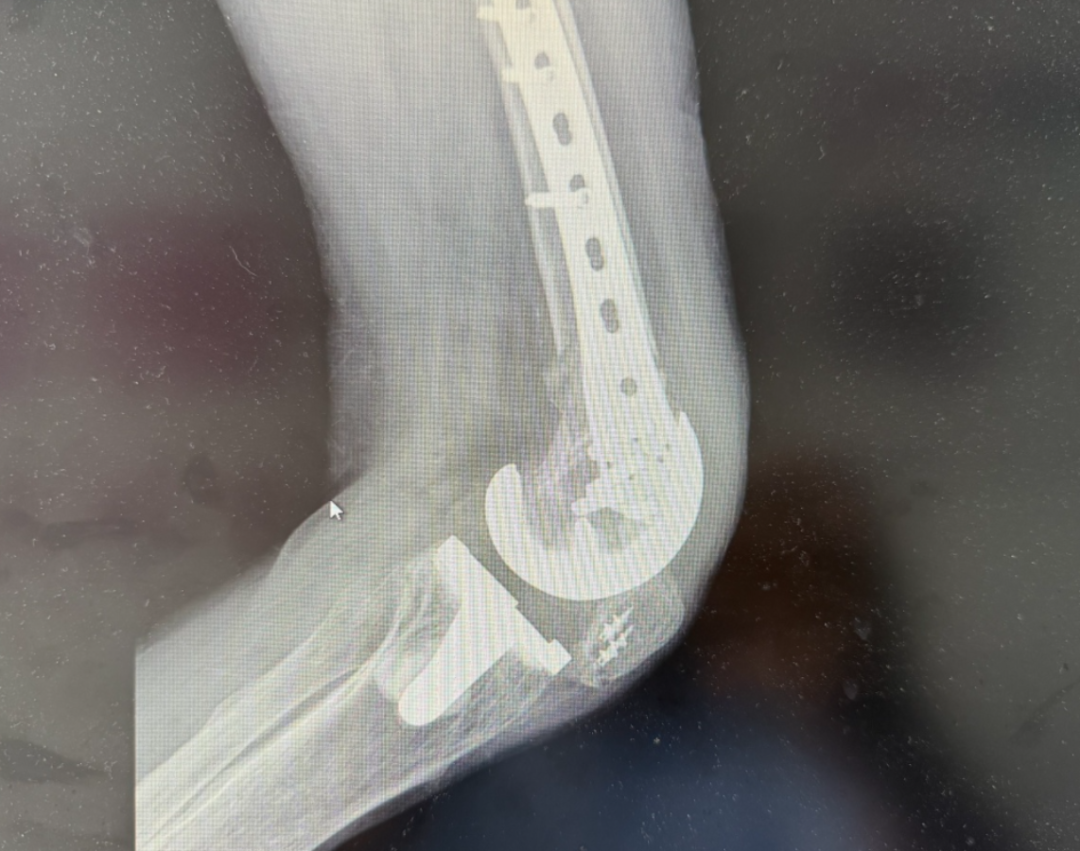

针对这一复杂的假体周围骨折病例,我院骨科团队进行了多学科会诊,制定了周密的"左膝假体周围骨折切开复位内固定术"方案。手术中,医生们精细操作,在保护原有膝关节假体和周围组织的前提下,精准复位骨折块并选用特殊锁定钢板固定。整个手术过程在影像设备实时监控下完成,这种精准的手术方式不仅成功修复了骨折,更保护了患者原有的关节功能,为术后康复奠定了坚实基础。

术后康复是恢复关节功能的关键环节。在医护团队的精心指导下,王大爷的康复过程分为三个阶段有序推进:首先控制术后肿胀和预防并发症,同时进行基础肌力训练;随后逐步恢复关节活动度并强化肌肉力量;最终实现安全负重行走和日常功能重建。通过医患双方的共同努力,复查显示骨折愈合良好,假体位置稳定,膝关节功能明显改善。如今王大爷已能借助助行器自如活动,生活质量得到显著提升。